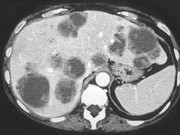

- 单项选择题男,54岁, 患者1年前行结肠癌手术,癌胚抗原增高, 影像检查如图,最可能的诊断为 ( )

A、肝淋巴瘤

B、多发结节性肝癌

C、多发性肝囊肿

D、多发性肝脓肿

E、结肠癌肝转移